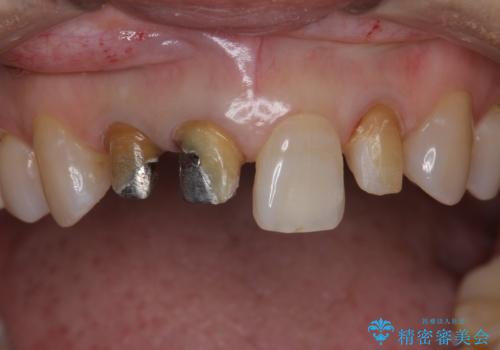

- 前歯のかぶせ物の際が黒いことを気にされて来院。

左上のかぶせ物になっていない歯は根の先に膿がたまっていたので根の治療をし、プラスチックでつぎはぎになっていたためセラミッククラウンでかぶせました。

右上12の二本の根の治療は特に行っておらずクラウンのみやり替えを行いました。